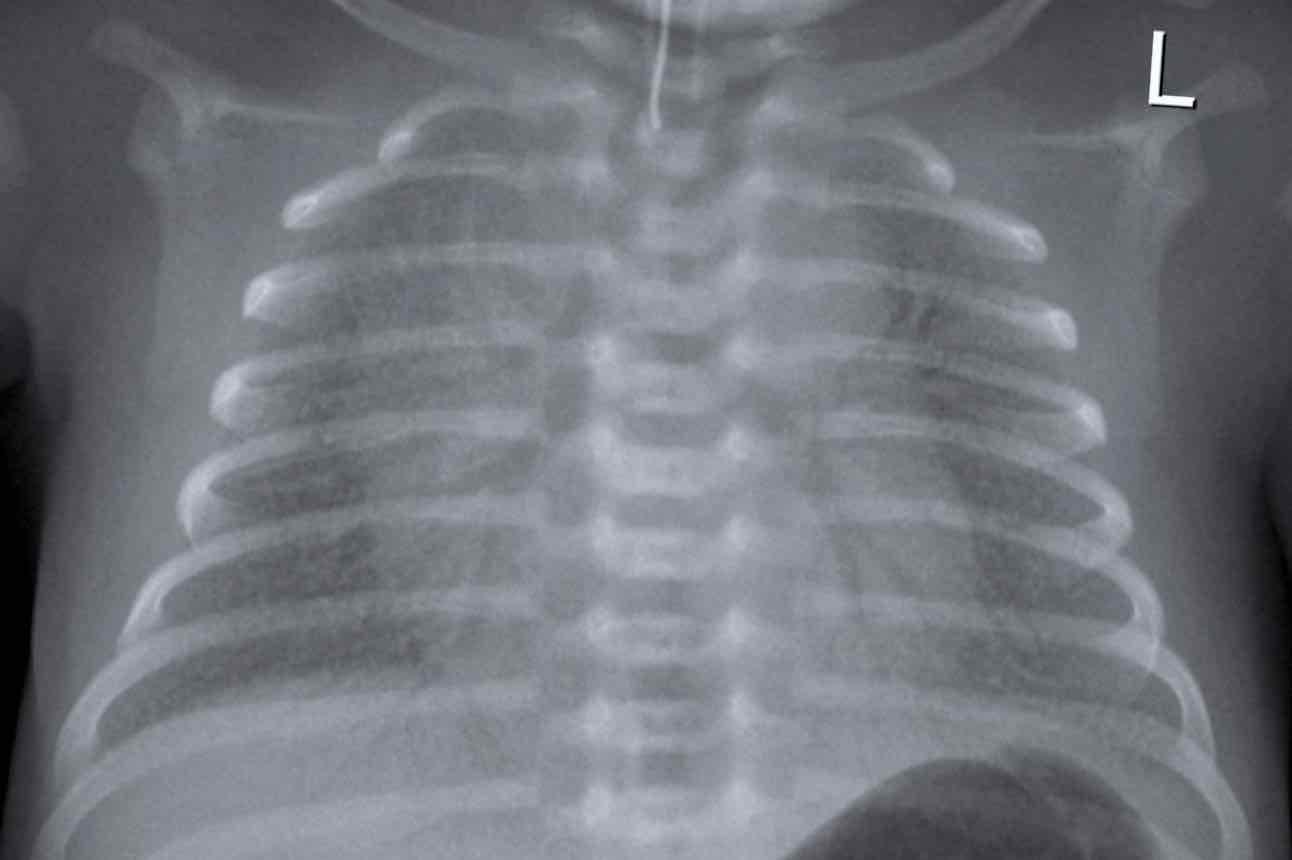

嬰兒胸部X光

如果BB有喘氣,會先照肺片查看有否肺炎症狀。